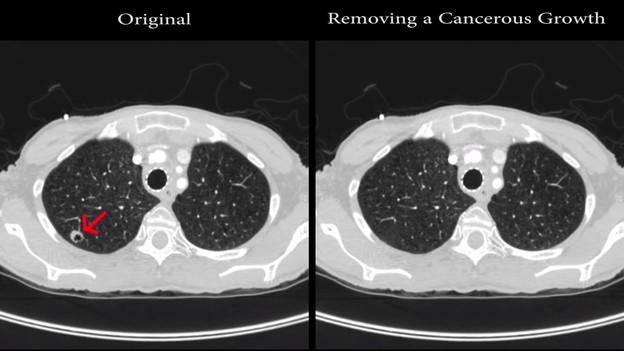

Malware može dodavati ili uklanjati rak sa slike u CT i MRI skenovima.

Istraživači iz izraelskog Ben Gurion University Cyber Security Research Centra, razvili su maliciozni softver koji može dodavati lažne tvorevine na CT i MRI skenove, ili uklanjati stvarne.

Kako bi testirali učinkovitost malwarea, istraživači su proveli studiju u kojoj su rekli radiolozima da dijagnosticiraju stanja temeljena na CT skenovima pluća, a neke od njih su mijenjali malicioznim softverom, kao što možete vidjeti u ovom videu.